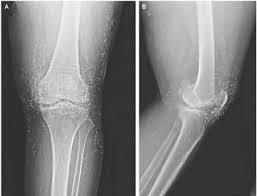

• antero-posterior (AP)central ray passes, perpendicular to the coronal plane, from anterior to posterior

• postero-anterior (PA): central ray passes, perpendicular to the coronal plane, from posterior to anterior

• lateral: central ray, perpendicular to the sagittal plane and parallel to the coronal plane, passes from one side of body to the other